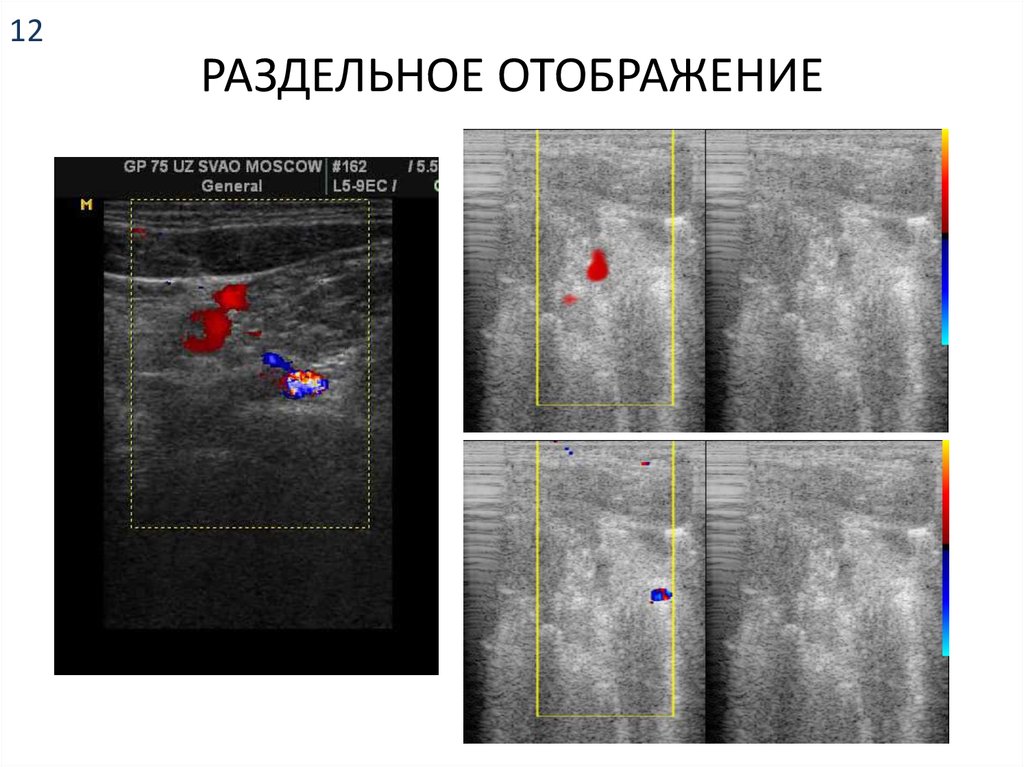

12. РАЗДЕЛЬНОЕ ОТОБРАЖЕНИЕ

12

РАЗДЕЛЬНОЕ ОТОБРАЖЕНИЕ

B

C